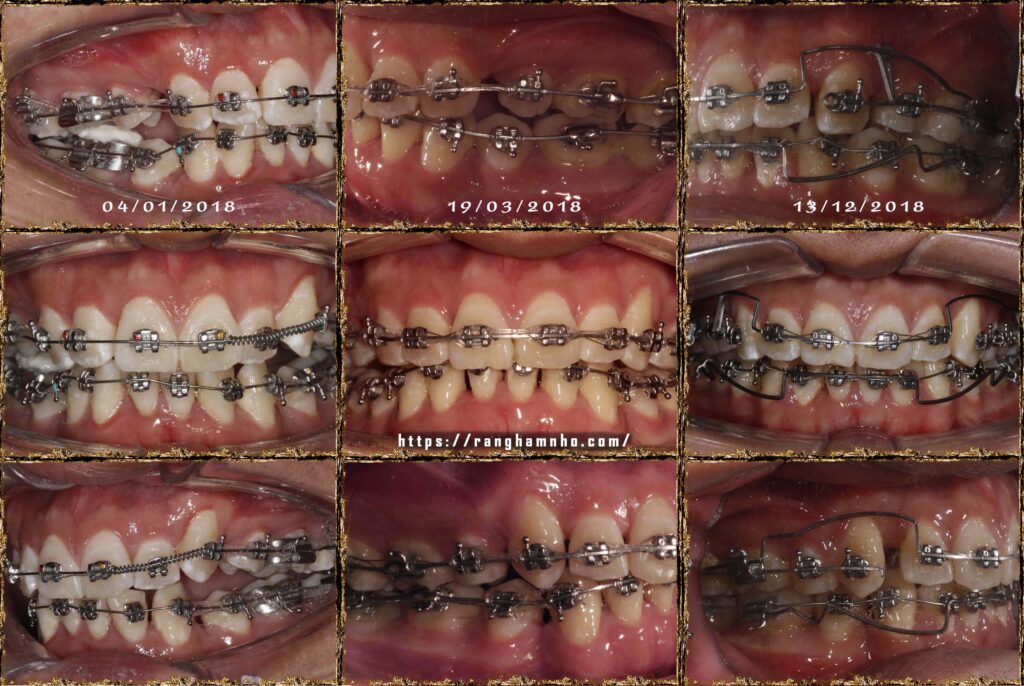

Bệnh nhân nam sinh năm 1998. Khớp cắn hạng I, với chen chúc và khấp khểnh nặng ở cả 2 hàm trên và dưới.

Cung hàm trên và cung hàm dưới đều hẹp, răng thiếu chỗ nghiệm trong.

Kế hoạch: Nhổ 4R4, chỉnh nha phân đoạn

Làm phẳng mặt phẳng cắn bằng cung tiện ích TMA 17×25 hai hàm